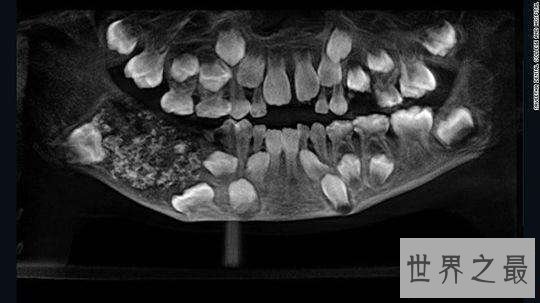

光片显示情况异常,医生决定为他做进一步的检查。手术发现,这名男孩的下颚上有一个明显的袋状肿块,里边包含526颗牙齿。

一位病理学家在承受新闻采访时表示:“这些牙齿让人想起牡蛎中的珍珠。”拔下来的牙齿总共约重200克,它们的大小各不相同,从1毫米到15毫米不等。每个牙齿上都连带一个覆盖着牙釉质的根状结构的冠。这个男孩在手术后第三天就出院了,拔牙后的他还剩下21颗牙齿,听说恢复的还挺好。

该医院的口腔颌面外科主任 Senthilnathan在承受《印度时报》的采访时表示:“他必须承受手术。他的下巴上有一个长满了小牙齿的囊,咱们必须十分小心肠取出来以确保囊不会裂开。但咱们并没有从旁边面将他的骨头凿开,因为这样会留下一个大洞,咱们是直接从顶部钻进去的。幸好肿块的位置并未与其他骨骼相连,并不需要进行颚骨重建。” 这种异常情况被称为复合性复质牙瘤。这是一种十分罕见的肿瘤,它会导致多个牙齿安排和牙齿样结构的生长。尽管这种肿瘤很难医治,但它们一般都是良性的。但目前尚不确认这种情况是由该男孩的基因因素、生长环境还是两者相互作用导致的。 尽管这种情况十分罕见,但也并非彻底闻所未闻。2014年,医生们从一名17岁男孩的嘴里取出了232颗牙齿。无独有偶,这也是在印度发生的事情。